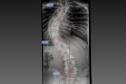

26/01/2026-Estrutura e equipe: Paraná é referência em cirurgias de deformidade da coluna vertebral

Paraná é referência em cirurgias de deformidade da coluna vertebral